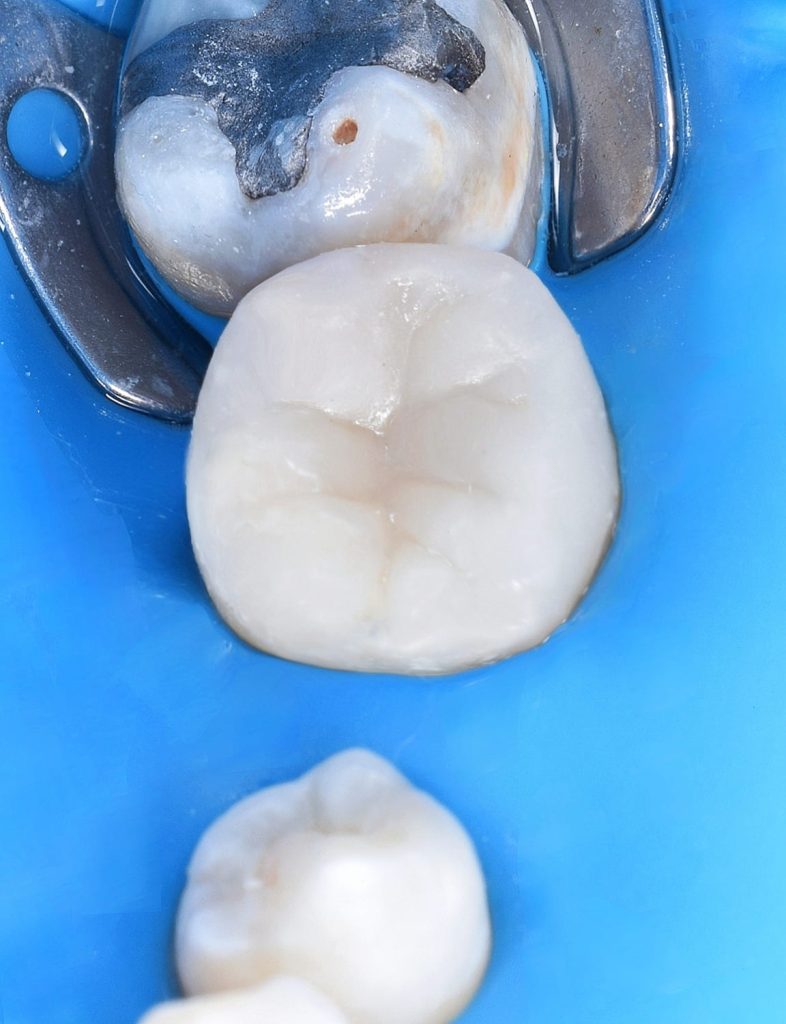

Pre operative situation

Multiple isolation

Direct view for isolation